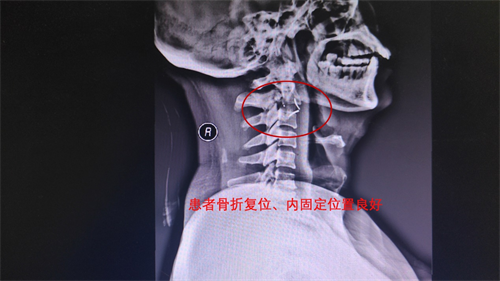

骨外科医生反复模拟推演,先后实施头皮撕裂伤清创缝合术、四肢骨折复位术等,逐步稳定患者病情状态,随后为其实施颈前路颈2/3椎间盘摘除+椎管减压+骨折复位+cage植骨融合术。手术过程顺利,术后患者康复迅速,X片复查显示,患者骨折复位、内固定位置良好。